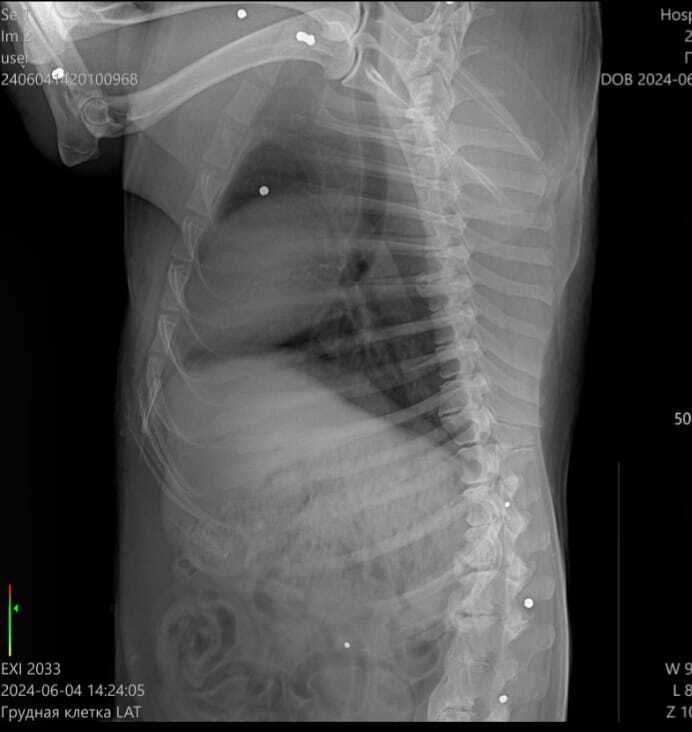

Друзья, в поселке Петрово живодёры стреляли в собаку. Бедный парень спрятался, пока люди не заметили, что с ним совсем беда. Состояние критическое: дробь в лапах, груди, морде; неизвестно, удасться ли сохранить одну из особо повреждённых лапок; множество травм по телу; некоторые ткани отмирают на глазах. Слов не хватает  описать весь ужас.

В данный момент за жизнь собаки борятся в клинике "Кранц Мур" в Зеленоградске. Нужна срочная помощь!